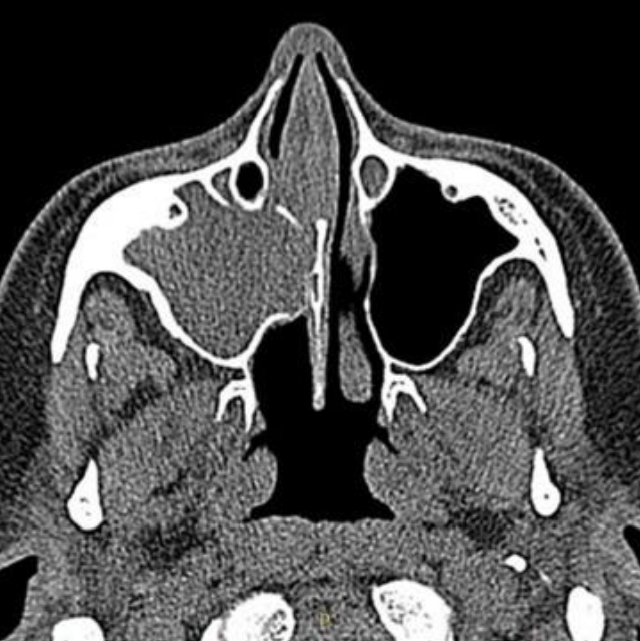

Imagem de tomografia computadorizada em janelamento de partes moles, no plano axial, demonstrando obliteração total do seio maxilar direito, associado a erosões ósseas da face nasal do mesmo. Seio maxilar esquerdo sem particularidades.